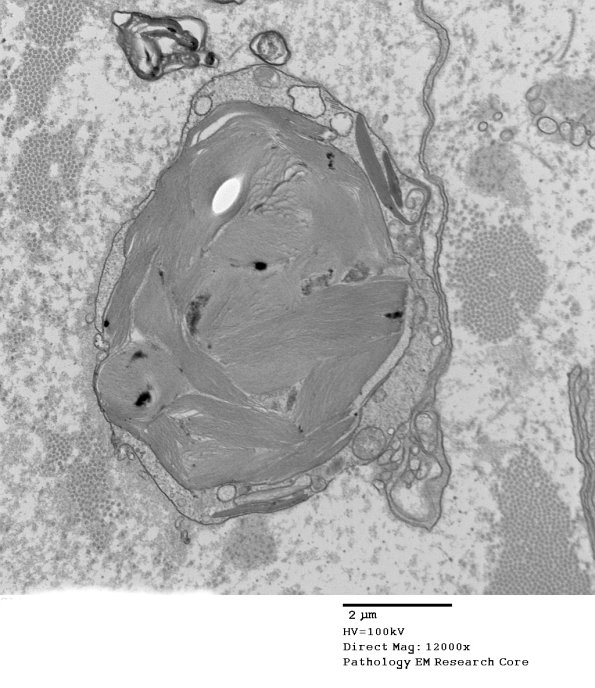

An enormous Pi granule in what appears to be a macrophage. (Electron micrograph)